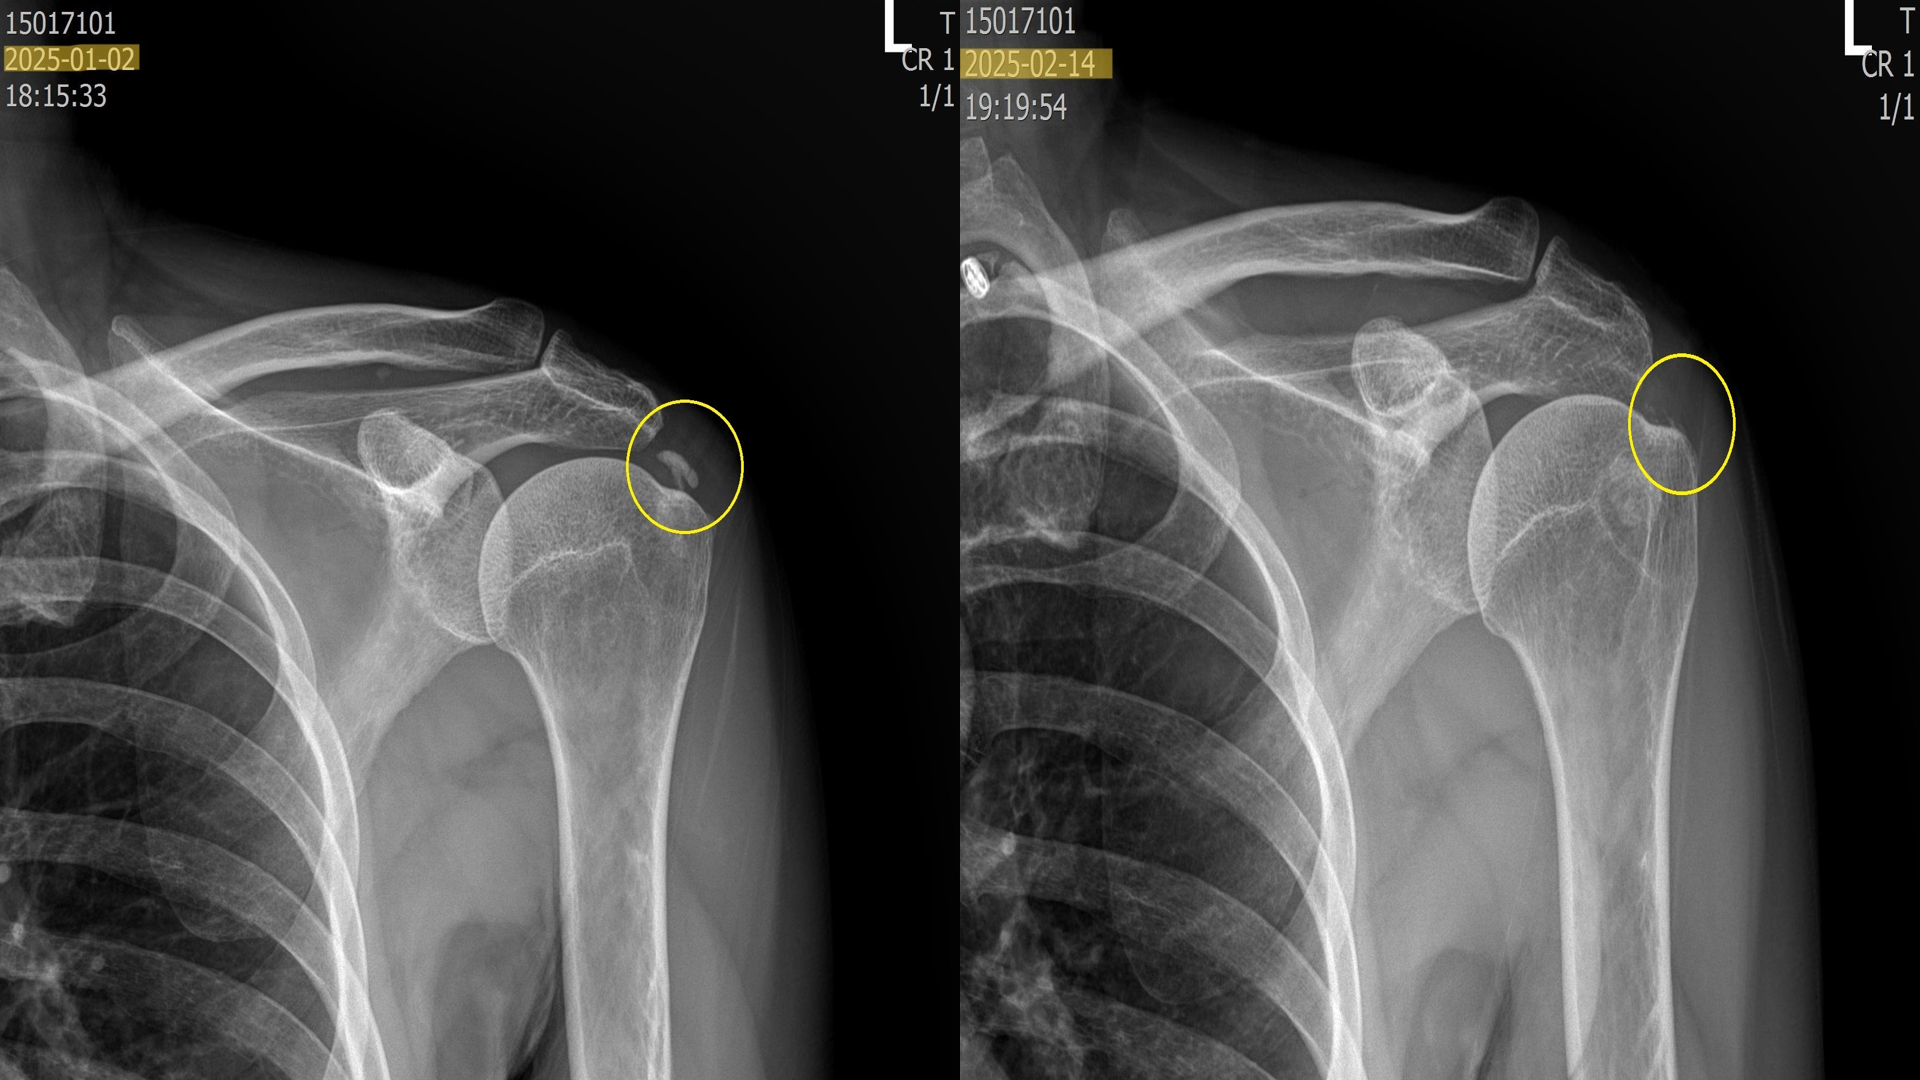

석회 흡입술 + 체외충격파 시술을 통해 석회가 얼마나 제거될까요?

위의 사진은 실제로 내원하여 치료받은 환자들의 x-ray 입니다. 이 환자분들은 약 5회에 걸쳐 섭회흡입술 + 체외충격파시술을 받은 분들입니다. 보시다시피 드라마틱하게 석회가 제거된걸 볼 수 있습니다.

혹시 석회성 건염으로 고생하시거나 진단받은 분이 있다면 섭회흡입술 + 체외충격파 시술을 함께 고려해보시길 바랍니다.